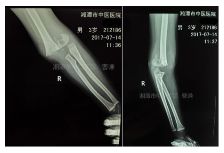

外院拍片情况如下:

GartlandⅢ型肱骨髁上骨折患者,患肢畸形、肿胀明显。肘前方可见皱褶,典型的难复型肱骨髁上骨折。